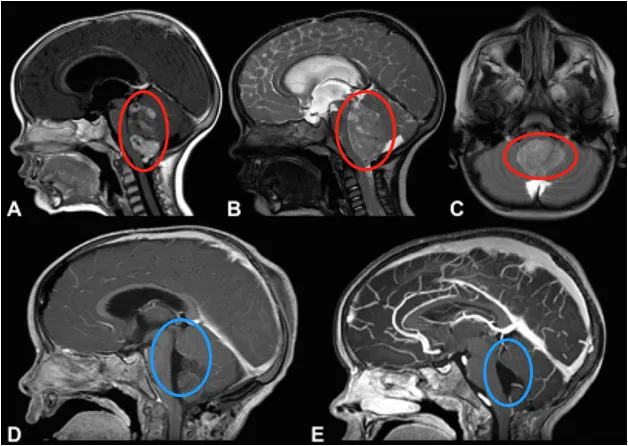

室管膜瘤在儿童常见的后颅窝肿瘤中位居第三,有四分之三的儿童室管膜瘤长在四脑室内,距离人体的生命中枢脑干非常近,如果治疗不当,很有可能危及生命。 然而,2025年8月发表于《LANCE...

颅内室管膜瘤是儿童常见的脑肿瘤,约占该年龄段所有中枢神经系统肿瘤的2%至9%。在该年龄段,室管膜瘤是仅次于星形细胞瘤和髓母细胞瘤的第三常见中枢神经系统肿瘤。其发病高峰在出生至...

切除范围是儿童幕下室管膜瘤患者预后的核心可调控变量。鉴于肿瘤与颅神经、重要血管结构之间存在紧密解剖毗邻关系,外科决策常面临最大化切除范围与平衡术后并发症损害之间的权衡。本...